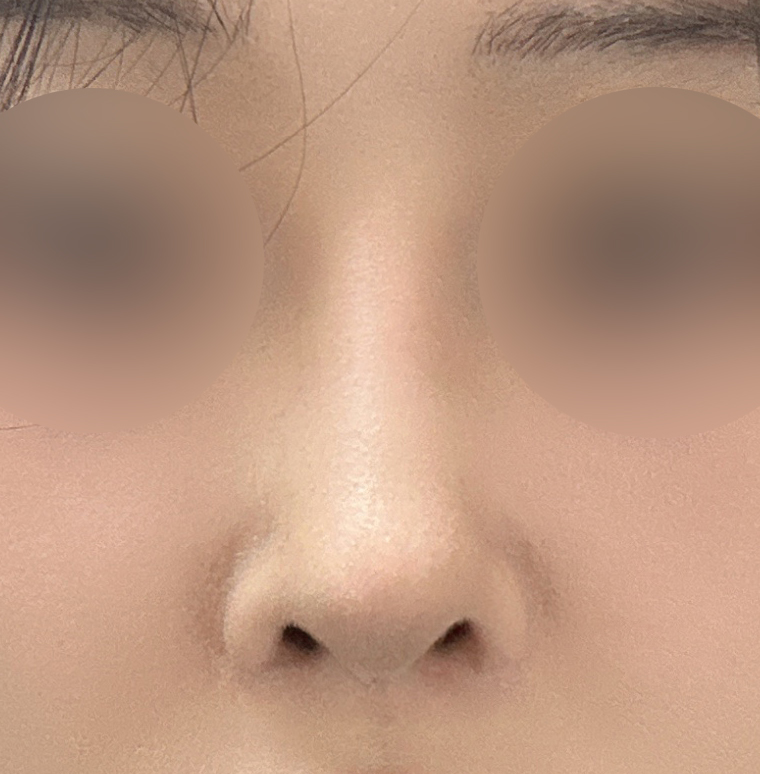

코수술받고 3주차됐어용

코수술을 받았고 지금은 3주차가 되었습니다.

실리콘, 비중격, 귀연골, 기증늑연골사용해서

수술했고 이물질제거와 복코, 용코교정한지

3주차 됐는데요

벌써부터 너무 자연스럽고

평소 고민이었던 용코도 정말 많이 교정되고

자연스럽고 화려한 코라인이 나와서

주변에서 칭찬 많이 받고 저도 너무 만족스럽고